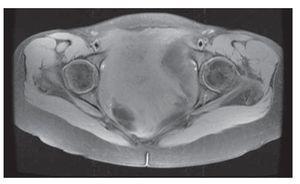

Mujer de 41 años de edad, sin antecedentes, que consultó por historia de dolor pélvico difuso, de baja intensidad, no irradiado, de ocho meses de evolución. Al examen físico se encontró una masa adherida a planos profundos y poco dolorosa a la palpación. Se le realizó una tomografía computadorizada que informó una extensa neoplasia pélvica de características malignas, que se extendía hasta el espacio isquiorectal, con desplazamiento y compresión de la vejiga y el útero, además de escaso líquido alrededor de la lesión (Figura 1). Se realizó una resonancia magnética nuclear que demostró una lesión de 14 x 14 cm, posiblemente de origen lipomatoso con degeneración mixoideangiolipomatosa, con probable infiltración al recto y sigmoides, dilatación pielo-ureteral bilateral por obstrucción del tercio distal de los uréteres (Figuras 2 y 3). Se realizó una colonoscopia que sólo evidenció desplazamiento del sigmoides por compresión extrínseca. Se le realizó una laparotomía exploratoria encontrando una masa pélvica de 15 x 20 cm, la cual se pudo separar de las estructuras adyacentes y resecar en su totalidad. El reporte histopatológico fue de una masa de 15 x 18 cm, con un peso de 260 g, de color amarillo-gris liso y opaco, de aspecto nodular y consistencia blanda. Al corte se encontraron áreas quísticas compatibles con angiomixoma (Figura 4). La paciente presentó una evolución satisfactoria, se le dio egreso. Actualmente se encuentra asintomática y sin datos de recurrencia.

Figura 4. La proliferación neoplásica muestra áreas mixoides hipocelulares alternando con otras de mayor densidad celular con infiltrado inflamatorio mixto y vasos curvilíneos hialinizados.